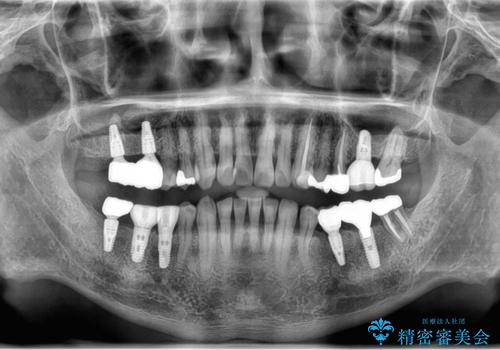

- 他院で奥歯が割れている為抜歯が必要と言われたとのことで来院。

右上56および左下5は割れていたためやむなく抜歯しインプラントにしていきました。

左下7(一番奥の歯)は抜歯をせずに済みましたが、高さがないため上の歯を矯正治療で沈め、また、歯ぐきの手術を合わせて行いクラウン(被せ物)をしっかり入れる処置をおこなっています。